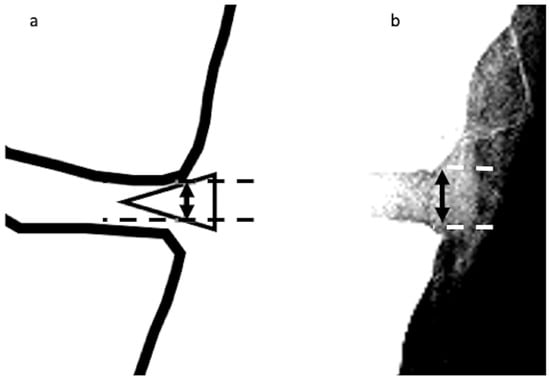

The MME length on radiographic images was investigated as follows. First, radiographs scanned in the knee anterior–posterior direction without weight bearing were subjected to appropriate window processing (specifically, narrowing the window width) to enable the medial meniscus to be more easily visualized (Figure 2). Next, the amount of MME (X-MME) from the medial margin of the tibia, excluding osteophytes (extrusion length) was measured (Figure 3), as was the height of the meniscus at the medial margin of the tibia, excluding osteophytes on X-ray (X-HMM) (Figure 4). Finally, the meniscal extrusion ratio was calculated by dividing the meniscal extrusion length by the meniscal height (X-MER) (Figure 5). Prior to these measurements, a small workshop to ascertain the appropriate gradation processing of radiographic images for use in meniscal measurements was conducted, using a radiology workstation (Synapse® Cardiovascular Picture Archiving and Communication System (PACS) (Fujifilm, Tokyo, Japan)). After the appropriate gradation processing method for measurements of MME length and meniscal height had been confirmed, two orthopedic surgeons specializing in the knee each made two sets of measurements, and intra-investigator reliability and inter-investigator reliability were calculated.

Figure 4. Height of the medial meniscus on X-ray (X-HMM). (a). A vertical line (solid line with arrowheads) is drawn intersecting the margin of the medial tibial plateau at the site of the transition from horizontal to vertical. The height is measured as the distance from the upper edge of the meniscus to the lower edge (dotted lines), as represented by the vertical line. (b) Measurement of X-HMM.